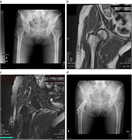

1. CTまたはMRIは有用で診断精度はきわめて高い(推奨度2J)

1. 高齢者の転位型(Garden stage III、stage IV)は人工物置換術を推奨する(推奨度1J)